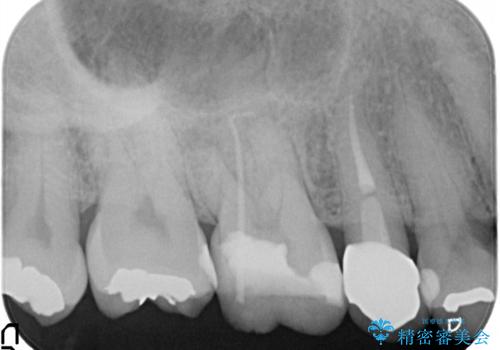

【根管治療】噛んだら痛い。ズキズキ痛い

- 4日前から噛んだ時に痛むことを主訴に来院された患者様です。

歯髄壊死/症候性根尖性歯周炎の診断のもと、根管治療を行なっております。

- 精密根管治療(イニシャルケース,大臼歯):122,000円、ファイバーコア:22,000円費用は治療当時の料金となります